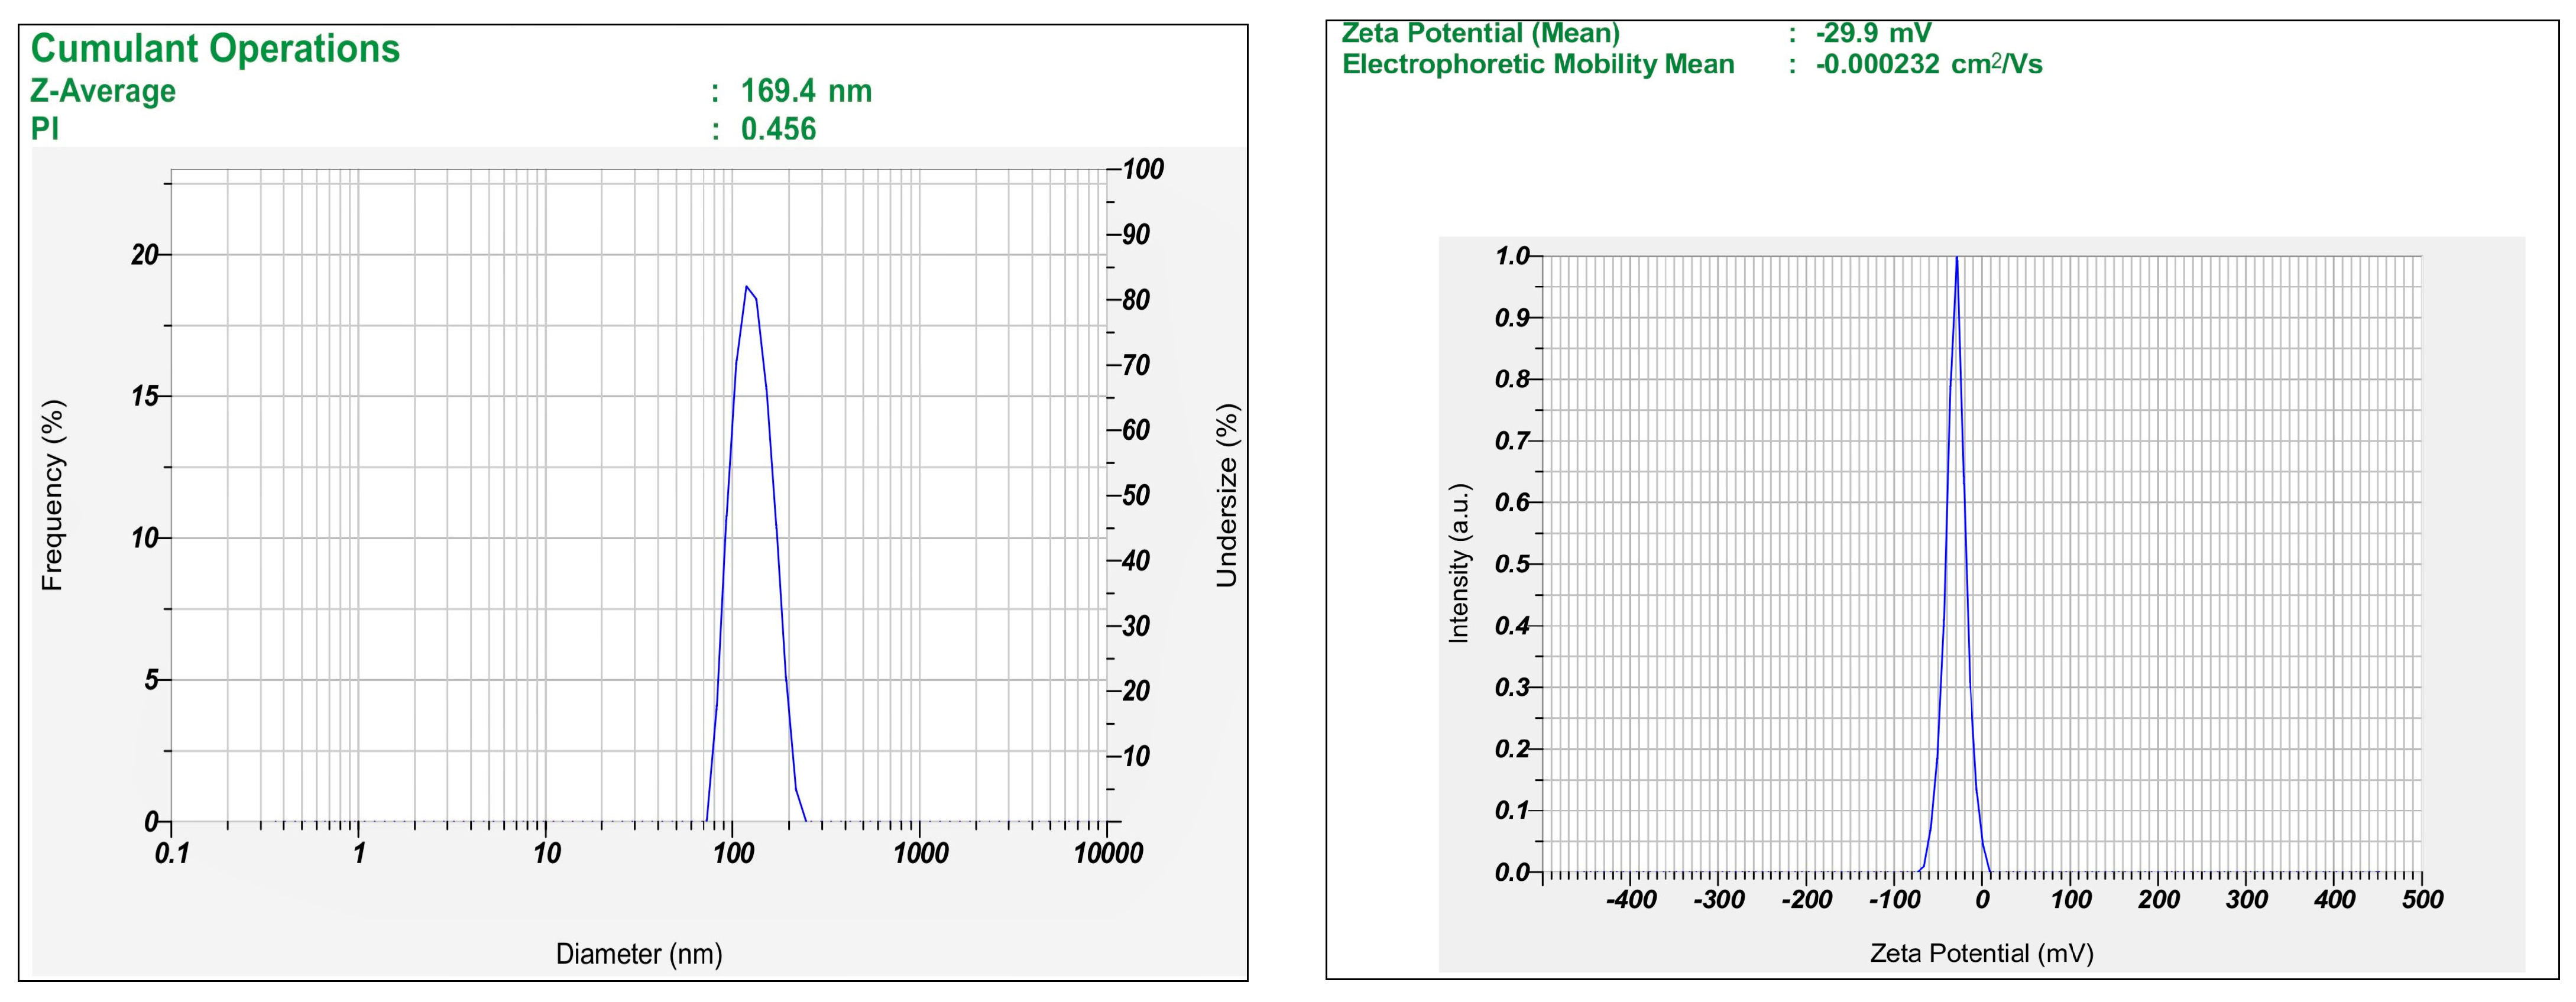

2.5. Characterization of MTX-Loaded Transferosomes

3.2.4. Size, Polydispersity Index, and Zeta Potential Analysis of Fabricated Vesicles

| Batch | Y1 Vesicle Size (nm) | Y2 Entrapment Efficiency (%) |

|---|---|---|

| B1 | 169.4 ± 4.4 | 69.22 ± 1.48 |

| B2 | 22.1 ± 3.9 | 45.14 ± 0.74 |

| B3 | 40.1 ± 4.9 | 13.92 ± 2.58 |

| B4 | 100.4± 0.1 | 33.85 ± 1.86 |

| B5 | 116.8 ± 3.2 | 17.91 ± 0.37 |

| B6 | 99.8 ± 2.1 | 33.94 ± 0.61 |

| B7 | 145.9± 0.5 | 39.52 ± 1.34 |

| B8 | 103.7 ± 1.6 | 33.47 ± 3.48 |

| B9 | 143.7 ± 1.4 | 56.42 ± 0.51 |